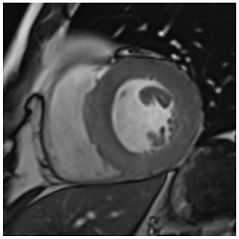

Table 3 summarises a suggested CMR scan protocol for the diagnosis of presumed HHD and differential diagnosis of patients with a “thickened left ventricle”.

Table 3.

The cardiovascular magnetic resonance protocol used for assessment of hypertensive patients. The described protocol can be acquired within 45–50 min. Images are examples from patients with hypertensive heart disease.

CMR stress perfusion essentially visualizes myocardial first-pass perfusion during pharmacological stress. Images are interpreted in conjunction with rest perfusion images and late gadolinium enhancement (LGE) images. In the presence of a significant epicardial coronary stenosis, the myocardial contrast uptake is reduced in a specific coronary territory (coronary pattern). Conversely, microvascular dysfunction displays a more diffuse and delayed but synchronous myocardial contrast uptake during stress. Stress CMR offers excellent sensitivity and specificity for the detection of anatomically and functionally significant CAD [37] and allows risk stratification irrespective of LVEF, the presence of CAD, symptoms, and LGE [38]. The assessment of quantitative myocardial blood flow has prognostic value and is likely to be used in the clinical routine in the near future [39].

To avoid the low but important risks of endomyocardial biopsy, which can have an overall complication rate of up to 6% [2], myocardial fibrosis can be assessed non-invasively using CMR: LGE is suitable for detecting irreversible replacement fibrosis and myocardial scarring and T1/ECV mapping for detection of potentially reversible (reactive) interstitial and more diffuse fibrosis (not detectable by LGE) (Figure 2).